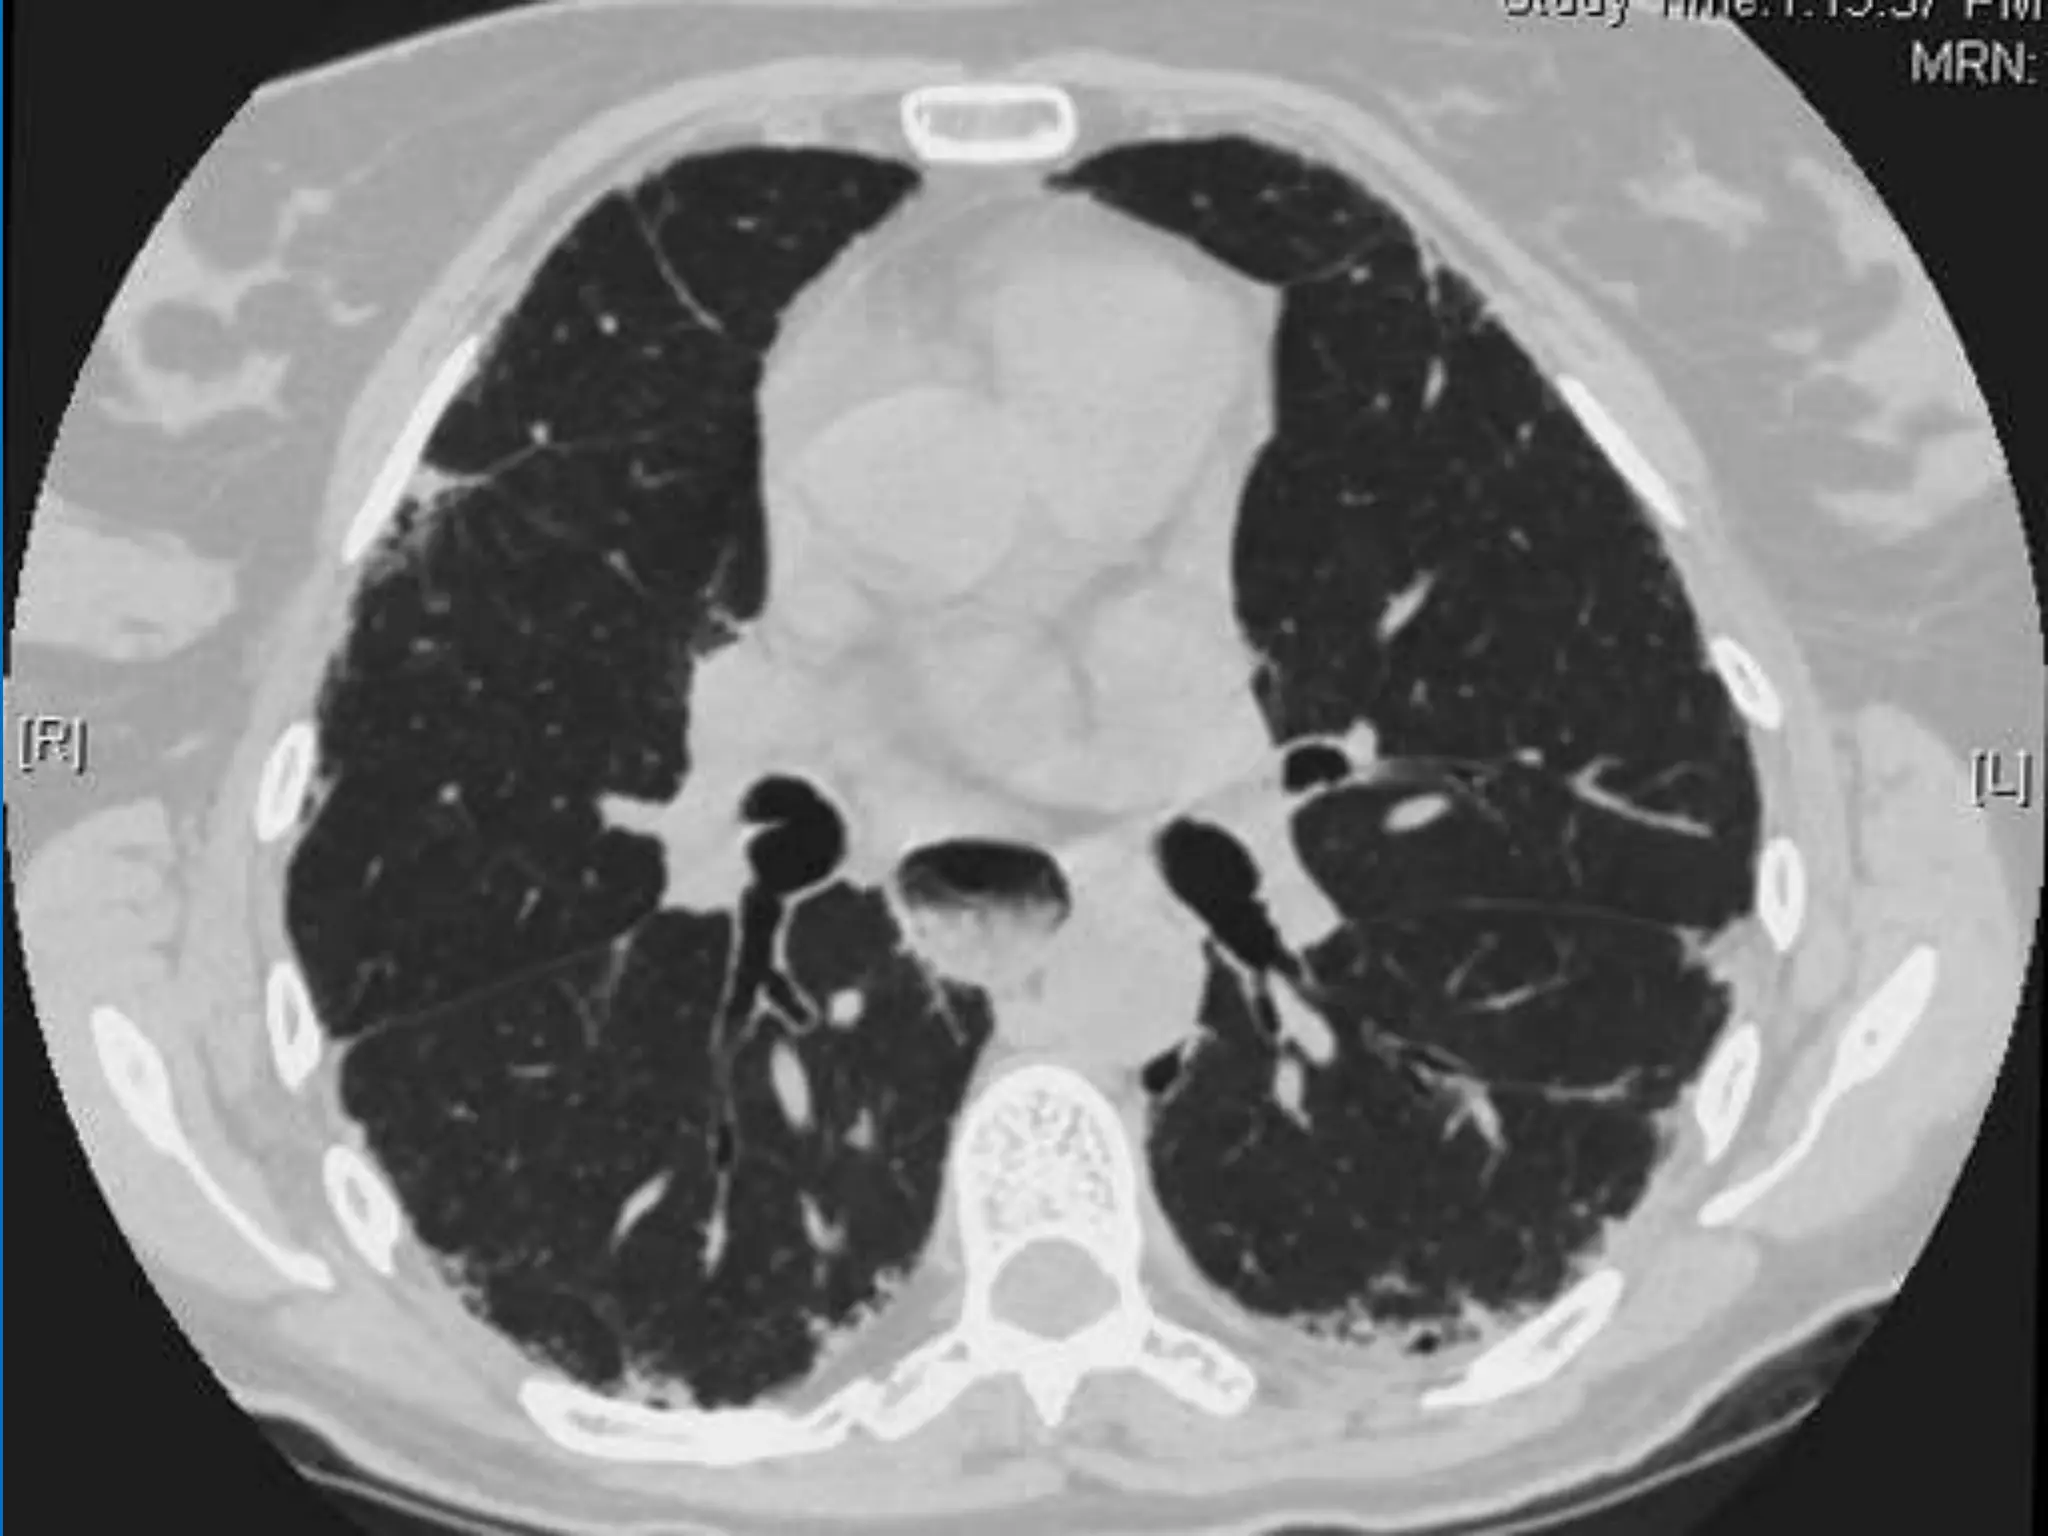

Scleroderma lung disease encompasses various respiratory complications, including interstitial fibrosis and alveolar ductitis, which are prevalent in patients. Recent research has identified differential gene expression in lung fibroblasts and new treatment options like antifibrotic and anti-inflammatory drugs. Despite the challenging prognosis, ongoing studies are promising in elucidating the disease mechanisms and potential therapeutic targets.